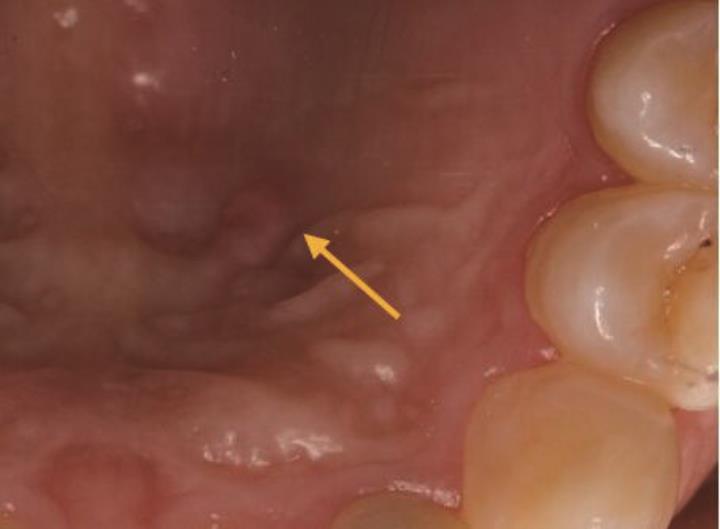

• 显微根尖手术治疗上颌侧切牙Oehlers Ⅲ型牙内陷1例

2024, 49(1):101-104. DOI: 10.13406/j.cnki.cyxb.003375

摘要 (34) HTML (13) PDF 9.96 M (122) 评论 (0) 收藏

摘要: